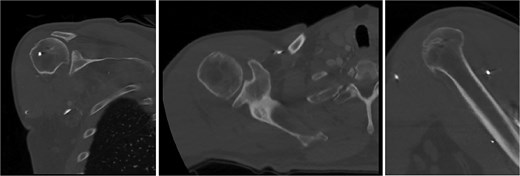

At 2 years after the initial injury, he continued to have right shoulder dysfunction, with forward flexion limited to 120°, external rotation limited to 30° with his arm at his side, and notable weakness with resisted external rotation at 4/5 strength despite injections, physical therapy, and arthroscopic debridement. Ultimately, he underwent rTSA with concurrent latissimus dorsi tendon transfer to address external rotation deficits associated with his posterior cuff deficiency. The subscapularis was additionally repaired using a medialized transosseous construct. He was maintained in an immobilizer for 6 weeks and then started formal therapy (Fig. 9).

Right reverse total shoulder arthroplasty at 3-month postoperative follow-up.